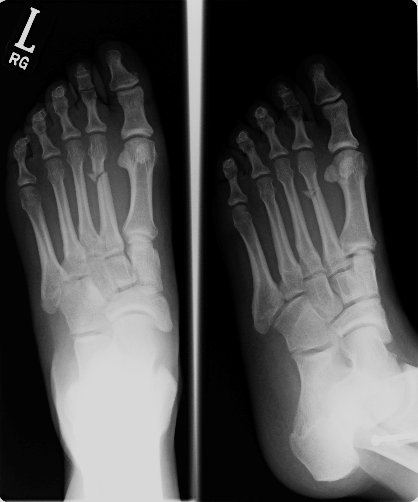

Return to Metatarsal Fracture